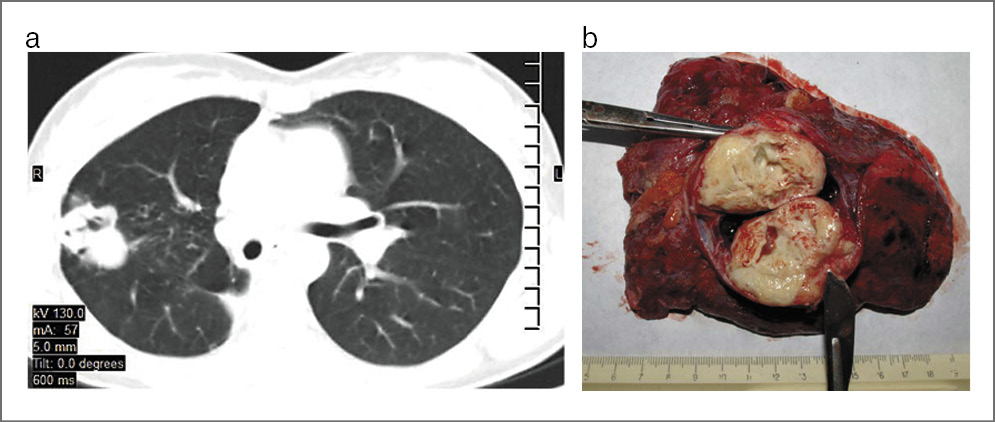

– Наиболее тяжелую клиническую ситуацию я описал в 2017 г. в журнале «Interactive Cardiovascular» [4]. Ко мне попала пациентка 46 лет, которая страдала туберкулезом легких в течение 13 лет. Несмотря на многочисленные курсы химиотерапии, сформировался ФКТ с тотальной деструкцией правого легкого и верхней доли левого легкого (рис. 7). Состояние осложнялось развившейся тотальной эмпиемой плевры с бронхоплевральным свищом. На основании посева мокроты у женщины определили ШЛУ-ТБ, а посев жидкости плевральной полости показал наличие Pseudomonas aeruginosa. Также у пациентки заболевание осложнилось амилоидозом почек, кахексией и дыхательной недостаточностью. Жизненная емкость легких при поступлении – 41% от долж., объем форсированного выдоха за 1-ю секунду – 25% от долж. Тест с 6-минутной ходьбой составил 270 м.

Рис. 7. КТ органов грудной клетки пациентки перед операцией. Определяется ФКТ с тотальной деструкцией правого легкого и верхней доли левого легкого.